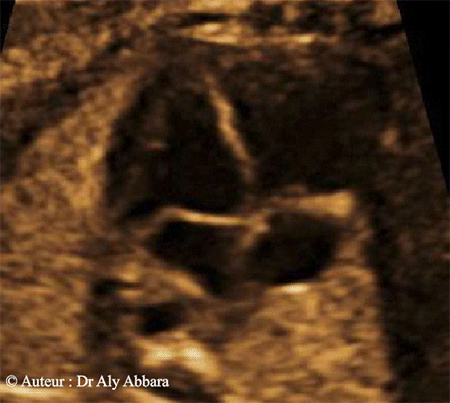

- I- Coupe des quatre cavités cardiaques

Sur cette coupe ; les éléments anatomiques suivants peuvent être mis en évidence :

- Le ventricule gauche (VG) et le ventricule droit (VD), puis le septum inter-ventriculaire séparant parfaitement ces deux ventricules.

- L'oreillette gauche (OG) et l'oreillette droite (OD), puis le septum inter-auriculaire séparant partiellement ces deux oreillettes ; en effet, l'oreillette droite communique avec l'oreillette gauche par l'intermédiaire du foramen ovale (une fenêtre située dans le septum inter-auriculaire).

- Les deux valves auriculo-ventriculaires droite et gauche, c'est-à-dire, respectivement : la valve tricuspide et la valve mitrale.

L'insertion de la valve mitrale sur le septum inter-ventriculaire est décalée légèrement vers le haut par rapport à l'insertion de la valve tricuspide sur le même septum (donc cette valve est légèrement plus bas par rapport à la valve mitrale).

- Une coupe transversale sur l'aorte descendante ; cette coupe est identifiable derrière l'oreillette gauche et légèrement à gauche du corps vertébral.